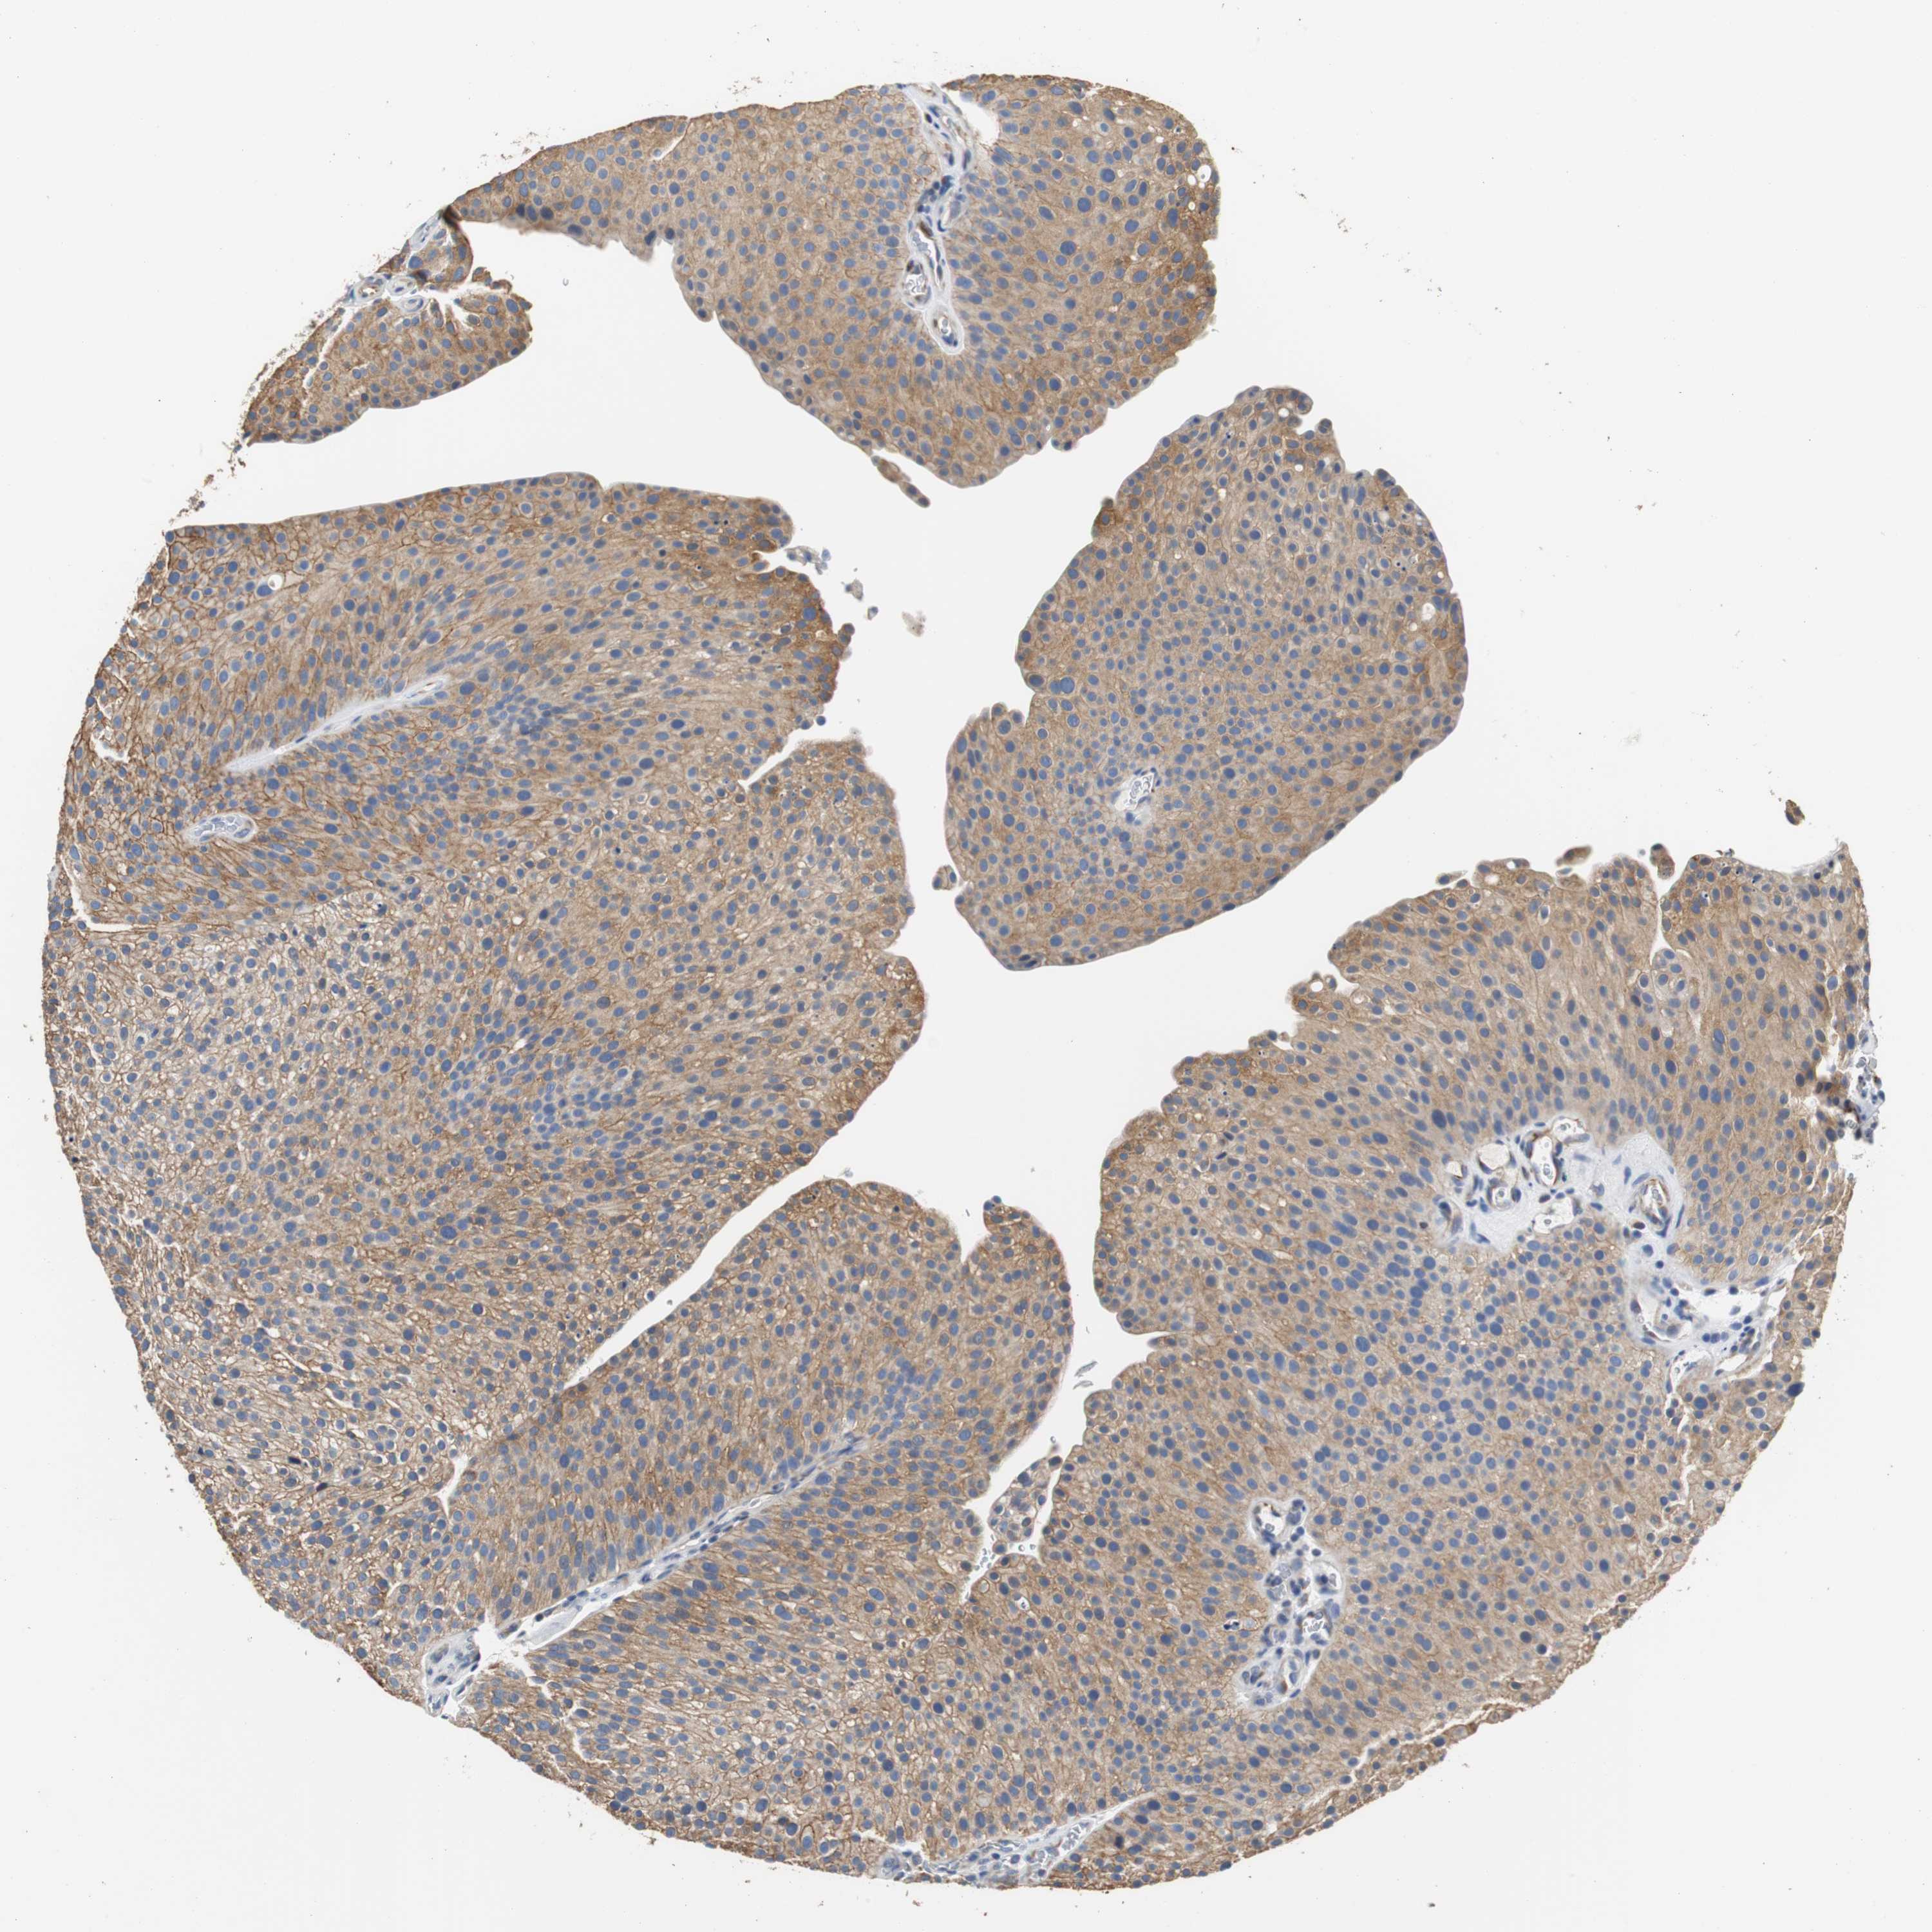

UROTHELIAL CANCER - Protein expressioni

A mouse-over function shows sample information and annotation data. Click on an image to view it in a full screen mode. Samples can be filtered based on level of antibody staining by selecting one or several of the following categories: high, medium, low and not detected. The assay and annotation is described here.

Note that samples used for immunohistochemistry by the Human Protein Atlas do not correspond to samples in the TCGA dataset.

Antibody stainingi

Antibody staining in the annotated cell types in the current human tissue is reported as not detected, low, medium, or high, based on conventional immunohistochemistry profiling in selected tissues. This score is based on the combination of the staining intensity and fraction of stained cells.

Each image is clickable and will lead to virtual microscopy that enables deeper exploration of all samples and also displays staining intensity scores, fraction scores and subcellular localization as well as patient and tissue information for each sample.

Antibody HPA006277

Antibody HPA006507

Antibody CAB017027

Staining

High

Medium

Low

Not detected

Intensity

Strong

Moderate

Weak

Negative

Quantity

>75%

75%-25%

<25%

None

Location

Nuclear

Cytoplasmic/membranous

Cytoplasmic/membranous,nuclear

Urothelial carcinoma, Low grade

Urothelial carcinoma, High grade